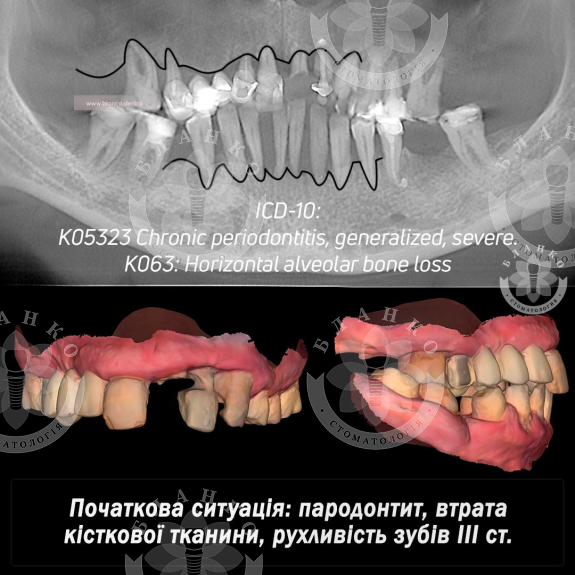

🧐🆘 Пациент обратился со следующей проблемой: генерализованный пародонтит на верхней и нижней челюсти, подвижность зубов, утрата костной ткани.